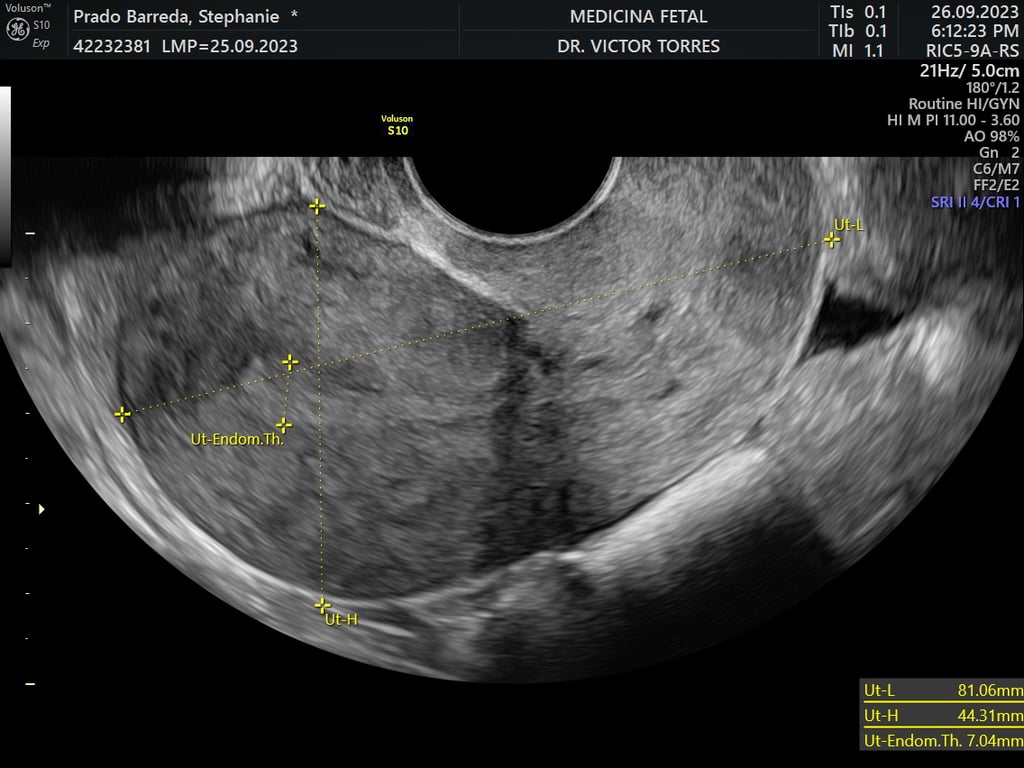

ecografía de viabilidad

4 - 11 semanas